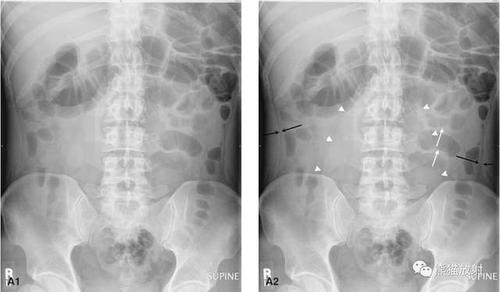

梗阻发生后的4~6小时,腹平片上即可见胀气的肠袢及多数气液平面.

肠梗阻的征象为腹部三个及以上高低不等呈阶梯状排列的气液平

急诊卧位及立位腹平片正常气腹小肠梗阻前哨肠曲